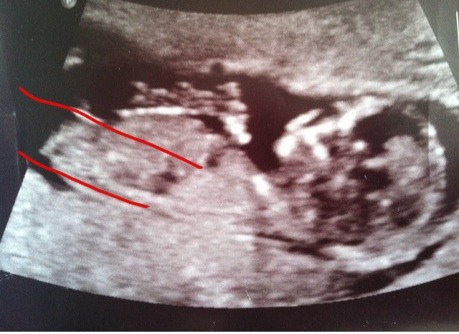

I wouldn't say you have no chance at seeing pink. I think it could go either way right now- and you definitely should not lose all hope at having a little girl. The nub looks pretty parallel to me (even with my slightly wobbly lines)..... Remember that these are just purely guesses and just because you've gotten boy guesses does not necessarily mean you are in fact having another boy. I've seen plenty of scans where the majority have guessed one gender and it turns out to be the opposite. When will you have your scan? My fingers are crossed for you!

Attachment 6631

Thanks jark22 for the words of encouragement. When you draw it out for me like that it does give me a twinge of hope. The fact that its not forking is really making me think boy...looks just like my ds2 but this one may be slightly less elevated than his. December 21st...ugh...just wondering if I should postpone it until after the holidays. This gd is hitting me hard although I am trying to stay upbeat for my fam.